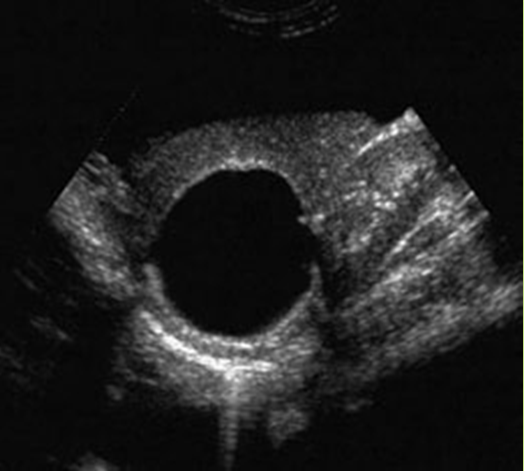

What is Simple hepatic cysts?

A hepatic cyst is usually a solitary, non-parasitic cyst of the liver. solitary or multiple. More common in females.

What is the sonographic appearance of hepatic cysts?

Solitary or multiple

Thin well-defined

walls

Anechoic

Posterior enhancement

Rarely fine,

linear internal septa, Calcification

What are the presenting symptoms of hepatic cysts?

Asymptomatic